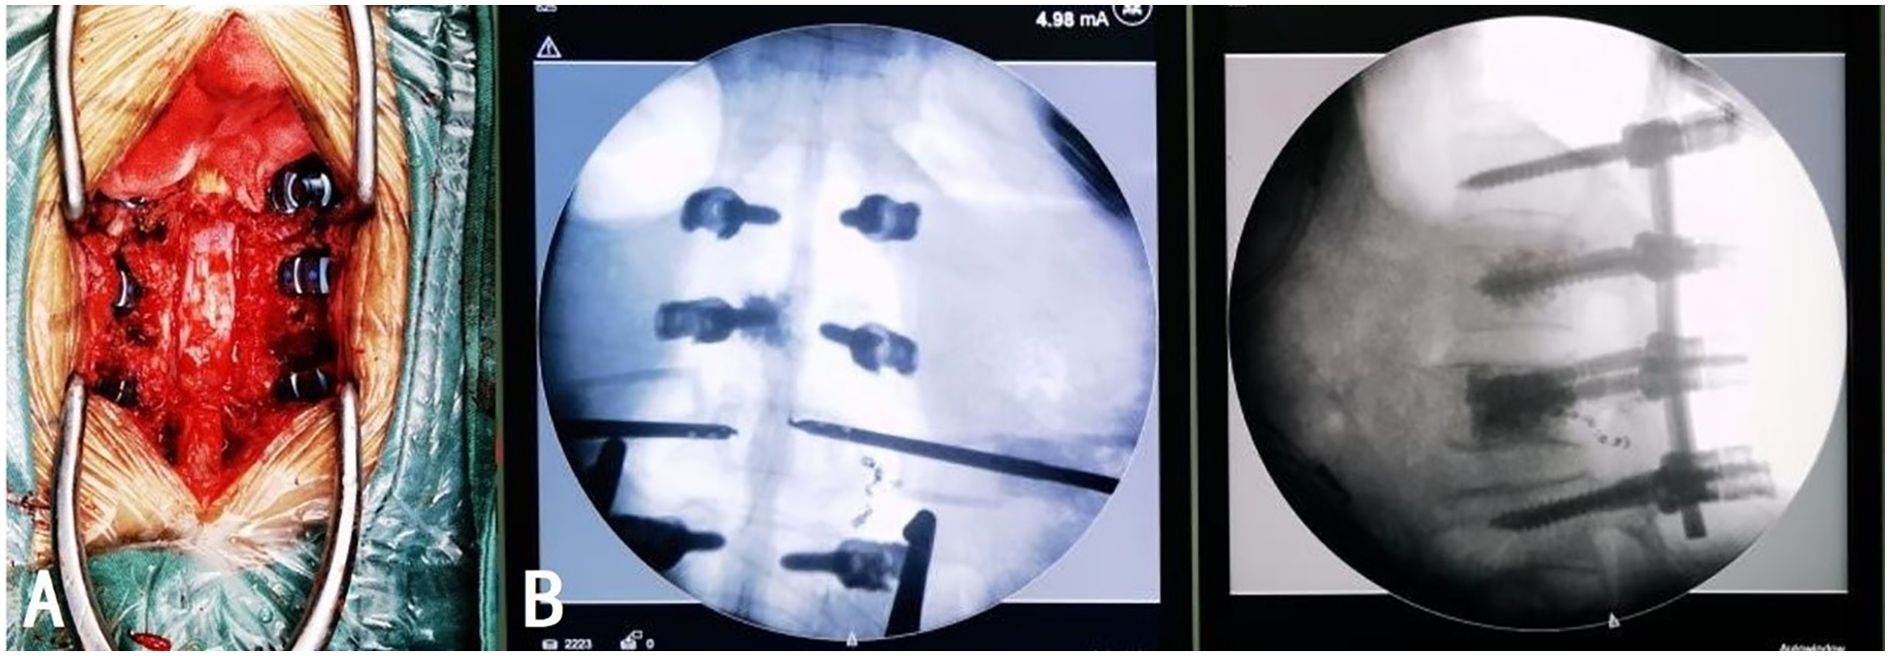

On day 6 post-admission, after the patient’s condition stabilized, L1 and L2 vertebroplasty, L1/2 and L2/3 total laminectomy, spinal canal decompression with bone grafting, and internal fixation were performed under general anesthesia. The patient was placed in the prone position and C-arm fluoroscopy was used to locate and mark the T12, L1, L2, and L3 vertebrae. A posterior median longitudinal incision of approximately 20 cm was made, the skin, subcutaneous tissue, deep fascia, and supraspinous ligament were sequentially incised, and hemostasis was performed. The bilateral paraspinal muscles were retracted to expose the bilateral facet joints from T12 to L3. Pedicle screws were implanted on both sides of T12 and L3, and on the right side of L1. Customized pedicle screws with channels were implanted into the pedicles on the left side of L1 and both sides of L2. Fluoroscopy revealed satisfactory screw placement. Tissue samples were obtained through the pedicle screw channels using a biopsy needle and approximately 3 and 6 mL of bone cement was slowly injected into the L1 and L2 vertebral bodies through the pedicle screw channels, respectively, under fluoroscopic guidance, ensuring no extravertebral leakage. The biopsy needle was slowly removed after the bone cement hardened. The L1 and L2 spinous processes were removed, an ultrasonic bone knife and lamina rongeur were used to remove the L1/2 and L2/3 laminae, and the removed laminae were trimmed into bone fragments for grafting. A pre-bent titanium rod was connected to the previously implanted pedicle screws, and the prepared bone fragments and artificial bone were impacted into the lateral posterior of T12, L1, L2, and L3. Fluoroscopy was utilized throughout the procedure to guide screw placement and verify the position of the rods and bone cement (Figure 4). After thoroughly rinsing with saline, hemostasis was achieved. The surgical instruments were counted to ensure that none were missing, the incision was sutured, and two drains were placed inside the wound. Intraoperative blood loss was approximately 500 mL, and 400 mL of type O Rh-positive plasma was transfused. The procedure was deemed successful. The patient was conscious, hemodynamically stable, and demonstrated good motor and sensory function in both lower limbs postoperatively.

Figure 4

A three-panel image includes: A) an intraoperative view of a surgical site on the spine with visible hardware and muscle tissue; B) an X-ray showing screws aligned in vertebrae; C) a lateral X-ray image of the spine with surgical screws and rods.

Figure 4. The position of the internal fixation under intraoperative direct vision (A) and fluoroscopy (B) was satisfactory. The distribution of the bone cement was appropriate without extravertebral leakage.